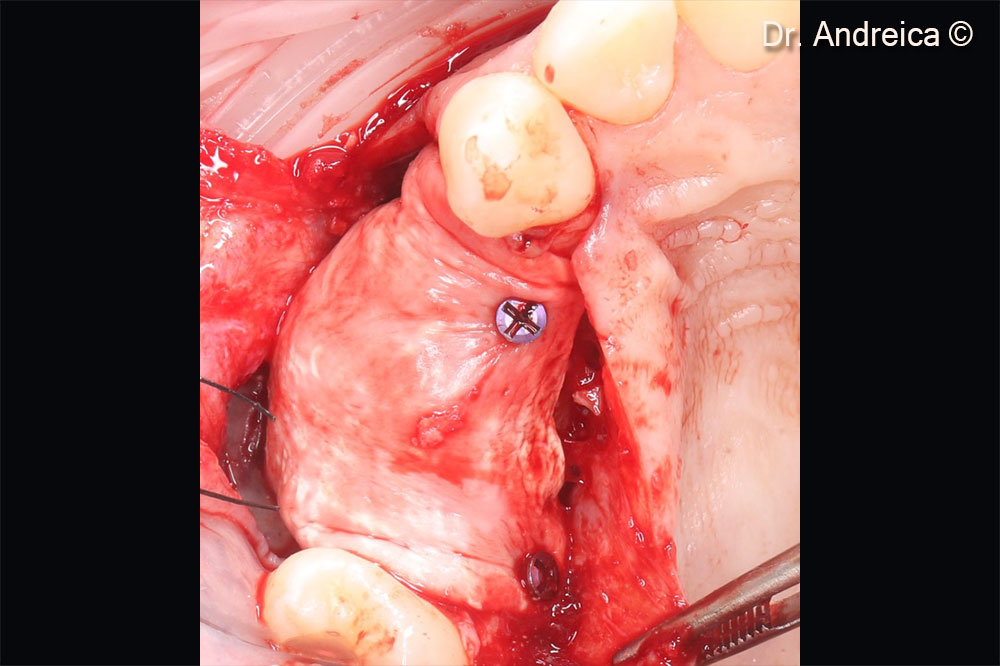

Evolution Membrane STD 30 x 30mm, trimmed and folded to cover the perforation and secure the crestal horizontal augmentation

The smaller part of the membrane coresponds to the sinus width and will be fixed under the schneiderian  membrane by the bone graft. The bigger part stays outside the sinus and will cover the horizontal graft

After filling the sinus and fixing the Evolution membrane we condense the bone mixture ouside the crest

Stretching of the membrane and fixation with titanium tacks. Overgraft to compensate shrinkage